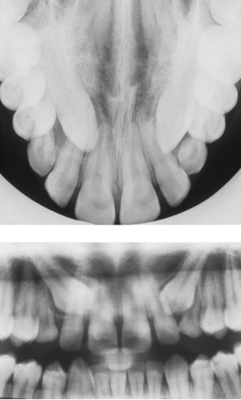

Is this impacted canine palatal or buccal to the centrals?

• palatal

• buccal

Is this impacted canine palatal or buccal to the arch?

Are these impacted canines palatal or buccal to the arch?